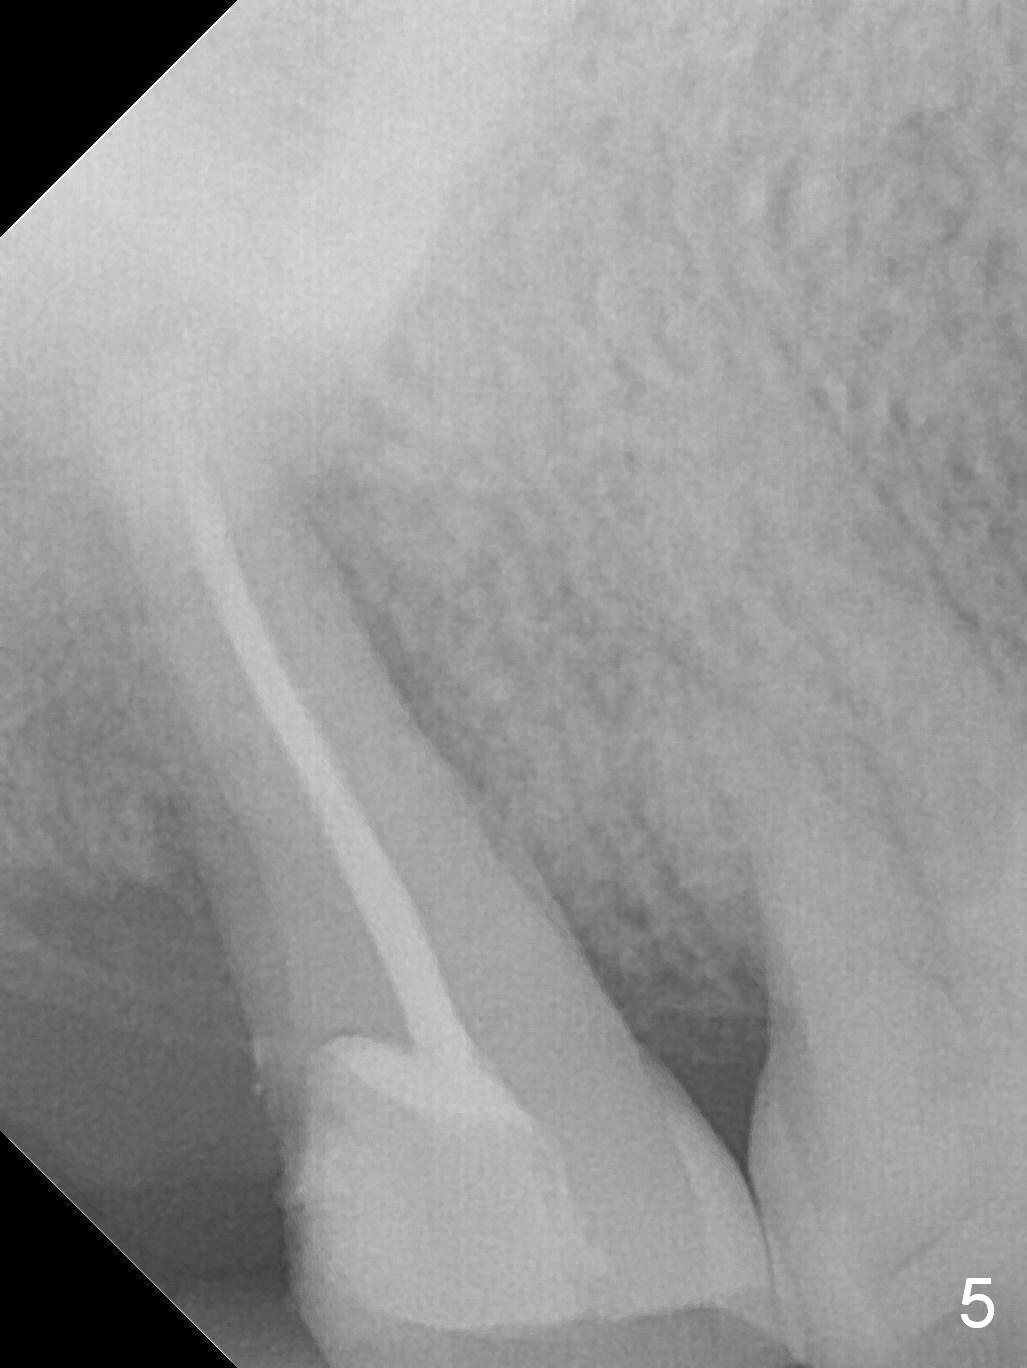

A 52-year-old woman presents to clinic with chief complaint "I can not bite in the upper right". Exam shows DO caries of the tooth #2 (Fig.1). After scaling & root planing and the tooth #1 extraction, pulpotomy is performed at #2. Two months later, pain recurs with swelling. When root canal therapy is finished at #2 (Fig.2-6), the tooth is found to have moderate mobility with guarded to poor prognosis. If the infection does not resolve, extraction and immediate implant seem to be necessary. Considering low bone density around the site of #2, a long implant is indicated (18 mm bone-level, Fig.7,8).